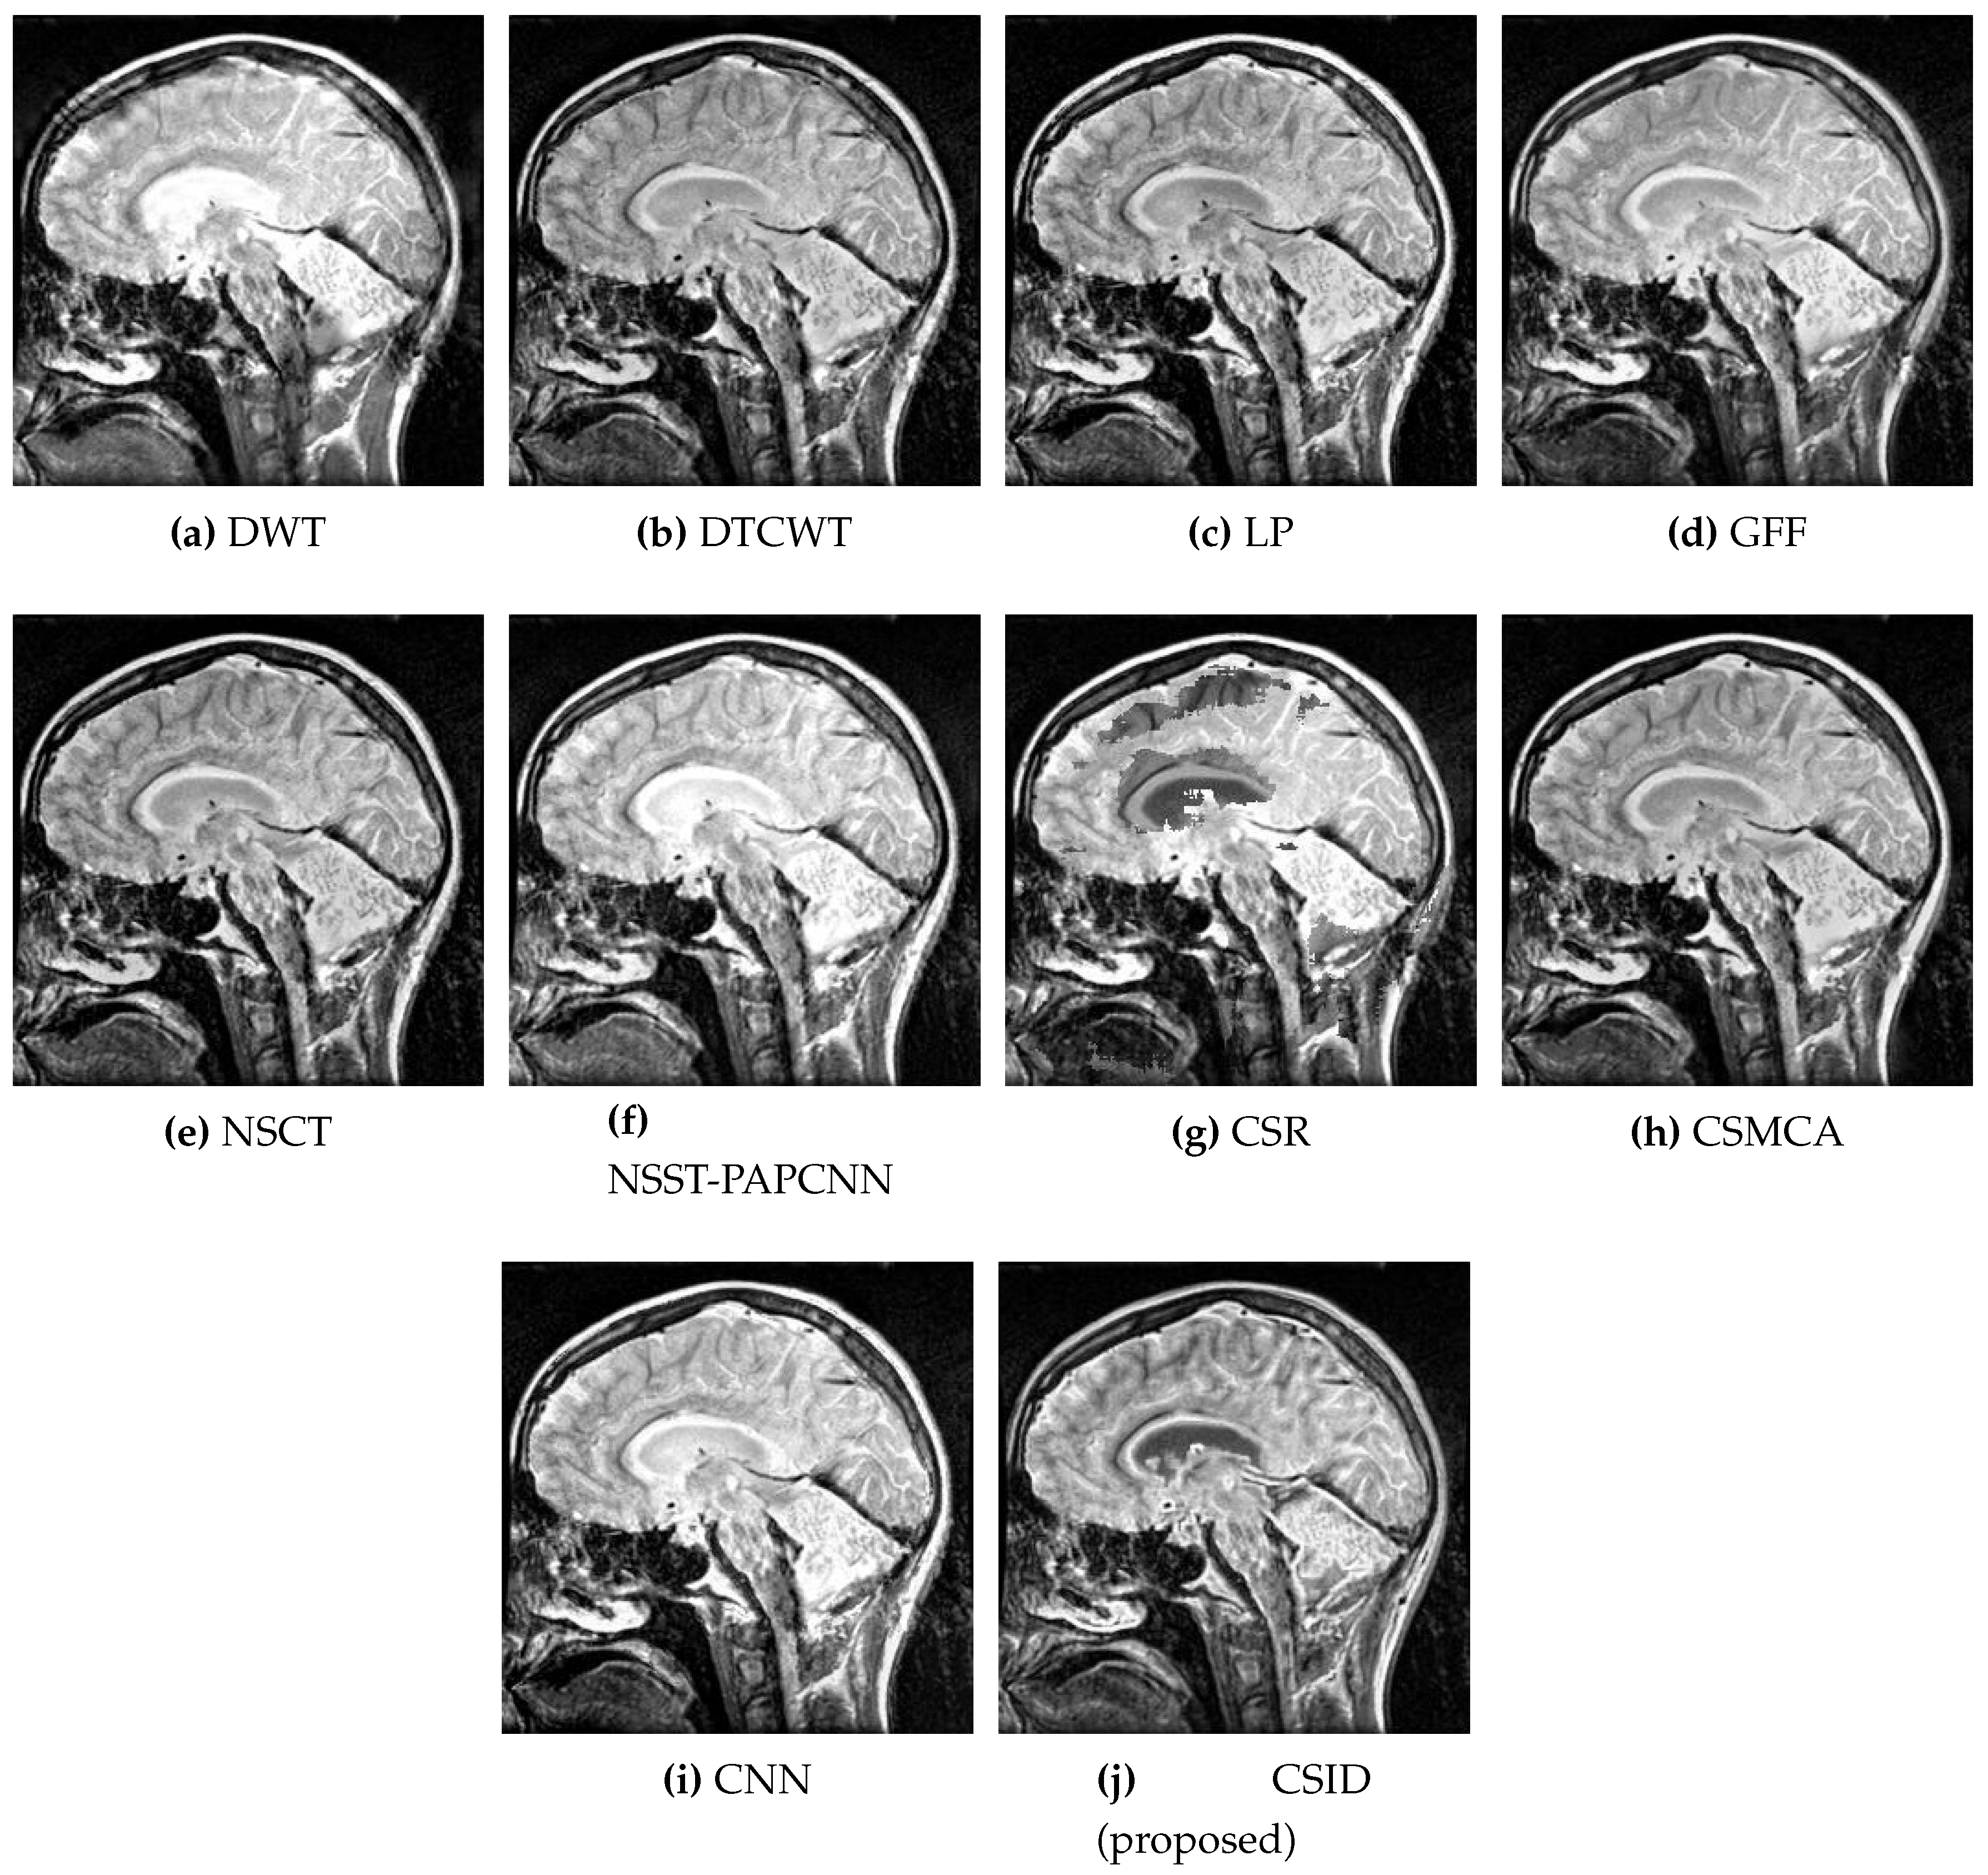

This subsection presents the results based on visual observations of the images generated through our proposed CSID algorithm in comparison with the aforementioned algorithms using different datasets, i.e., Data-1 through Data-6. Visual quality comparison of the Data-1 dataset using different fusion methods, i.e., DWT, DTCWT, LP, GFF, NSCT, NSST-PAPCNN, CSR, CSMCA, CNN, and the proposed algorithm are shown in Figure 5a through Figure 5j, respectively. A CT image gives information about hard tissues and their structures, whereas an MRI image indicates information regarding soft tissues. For better diagnosis, it is essential to merge critical information of the aforementioned images into one fused image [12]. In this regard, the aforementioned set of algorithms perform multimodal image fusion. The qualitative results shown in Figure 5 depict inferior performance, in terms of contrast and visual effect, for DWT (Figure 5a), DTCWT (Figure 5b), NSCT (Figure 5e), and CSR (Figure 5g). Note that these algorithms are not capable of preserving information in the fused image, which relates to the objective evaluation metric MI that remains proportional to the level of information extraction. Additionally, Section 5.2.2 further validates this claim through quantitative analysis, where DWT, DTCWT, NSCT, and CSR exhibit lower MI score in comparison with other algorithms. Moreover, GFF (Figure 5d) and NSST-PAPCNN (Figure 5f), yield better results, when compared with DWT, DTCWT, NSCT, and CSR algorithms, by avoiding information loss. However, the lack of noise removal results in over enhancement of the structural features in these algorithms. CSMCA (Figure 5h) and CNN (Figure 5i) further improve the visual quality, where enhanced visualization remains an outcome of lesser information loss. Finally, our proposed CSID algorithm (Figure 5j) yields clear, high contrast and superior visual quality and preserves the salient features, which include considerably enhanced bone structure and soft tissues information in comparison with other given algorithms.

Figure 5. Comparative analysis, based upon visual observation, of the resultant fused images generated by the given set of algorithms using Data-1 dataset.

Diagnostics 10 00904 g005